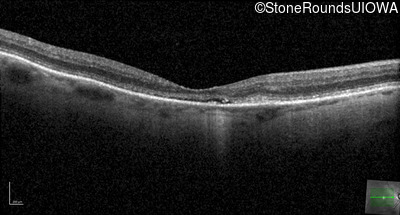

The clinical features favoring the diagnosis of RP1L1-associated occult macular dystrophy include: reduced acuity with a near-normal ophthalmoscopic appearance, a history of normal acuity in childhood; and, a "moth-eaten" appearance of the macular ellipsoid zone on OCT.

Age at visit: 72 years